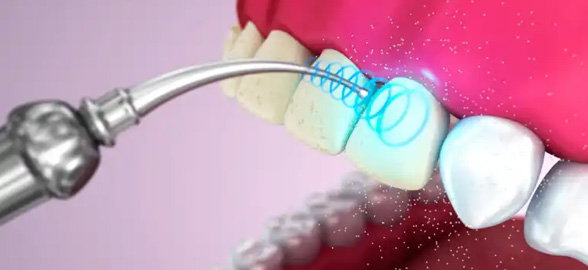

Dans la dentisterie moderne, les pointes à ultrasons ont révolutionné la manière d'aborder les traitements dentaires.